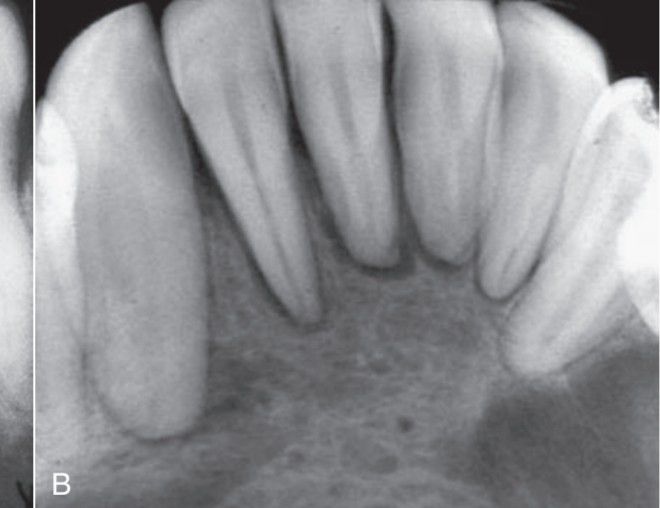

Hyperparathyroidism associated with loss of lamina dura around roots.